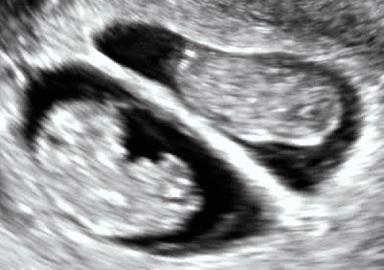

Abdominal ultrasonography of monoamniotic twins at a gestational age of 15 weeks. There is no sign of any membrane between the fetuses. A coronal plane is shown of the twin at left, and a sagittal plane of parts of the upper thorax and head is shown of the twin at right.